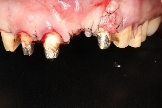

左側側門牙進行牙肉增生手術,解決牙齦萎縮問題。

左側正中門牙缺牙,缺牙處植入人工牙根。